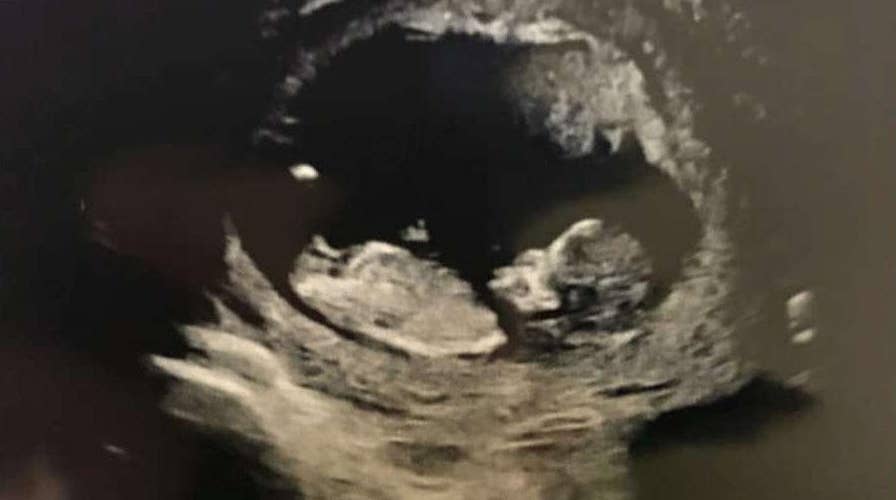

Jedediah Bila and her husband's first child will be a baby boy!